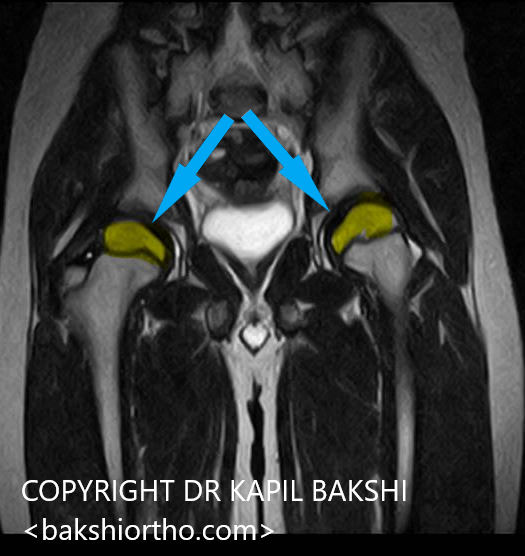

Previous ImageNext Image Perthes medial flattening Shahzaib.3.JPG MRI Scan shows bilateral involvement Like Loading...